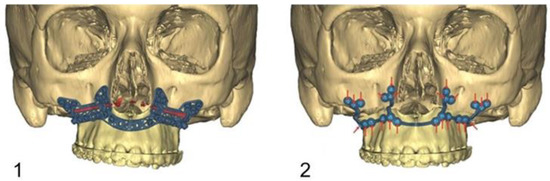

The transfer of the planned maxillary position into the surgical site is conducted waferless with a laser-melted CAD/CAM drilling/osteotomy template and a laser-melted CAD/CAM PSI.

The drilling/osteotomy template and the PSI was designed and manufactured by Materialise© (Leuven, Belgium) after an online planning session with the responsible surgeon team. In the planning, the pre-drilled holes and the osteosynthesis screws were positioned in such a way that the tooth roots were spared (Figure 2). The drilling/osteotomy template is passively and temporarily fixed to the maxillary bone with two to a maximum of four additional osteosynthesis screws. The holes for the subsequent osteosynthesis are then drilled both cranially and caudally to the osteotomy using the drill/osteotomy templates preformed drill channels. The Le Fort I osteotomy line is guided in the area of the anterior and lateral walls of the maxillary sinus as virtually planned and is completed after removal of the drill/osteotomy template. After “down fracture”, the patient-specific implant is passively placed on the caudal mobile maxilla and fixed with screws through the already predrilled holes. The design and shape of the patient-specific implant encodes the final position of the maxilla in all three planes with a secure and reproducible fit (Figure 3). Therefore, the maxillary positioning can be performed intraoperatively, independently of the mobile mandible. The maxilla is moved cranially until the empty screw holes of the PSI are also passively positioned over the pre-drilled holes in the cranial part on both sides of the midface. The PSI fixation follows by using monocortical osteosynthesis screws with a diameter of 1.85 mm and a typical length of 4 mm (Figure 4).

Figure 2.

Virtual computer-assisted planned drill/osteotomy guide with protection and consideration of the maxillary dental roots.

Figure 3.

Image (1): Computer assisted designed drill/osteotomy template with the Le Fort I osteotomy line (red), the drill channels for the temporary fixation of the template, and the drill channels for the subsequent definitive osteosynthesis with PSI. Image (2): New positioned maxilla after definitive osteosynthesis with PSI (red arrows= inserted osteosynthesis screws).

Figure 4.

Image (1): PSI fixed with osteosynthesis screws caudally to the maxillary osteotomy line. Image (2): Definitive fixation of the PSI after cranial mobilisation of the maxilla until it overlaps the predrilled holes.